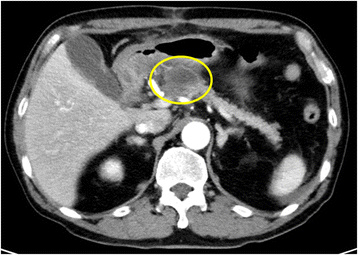

Acute Pancreatitis Pseudocyst. Pseudocysts which occur after acute pancreatitis have a different course as compared to those appearing after chronic pancreatitis so that a distinct treatment is also needed 6 19 20. Pancreatic pseudocysts are usually complications of pancreatitis although in children they frequently occur following abdominal trauma pancreatic pseudocysts account for approximately 75 of all pancreatic masses. The presence of pseudocysts may create complications in the cases of acute pancreatitis. There was no significant difference in the spontaneous resolution rate between both groups.

People with chronic pancreatitis can also get pseudocysts. A pancreatic pseudocyst is a collection of tissue and fluids that forms on your pancreas. There was no significant difference in the spontaneous resolution rate between both groups. Pseudocysts affect acute pancreatitisin10 to 23 of the patients. Pancreatic pseudocyst developed in 14 6 of acute pancreatitis and in 41 8 of acute on chronic pancreatitis p 0 00. Approximately 14 6 of the patients who experience acute pancreatitis are expected to develop a pancreatic pseudocyst as a complication.

Pseudocyst is a common complication of acute and chronic pancreatitis. People with chronic pancreatitis can also get pseudocysts. A pancreatic pseudocyst is a circumscribed collection of fluid rich in pancreatic enzymes blood and necrotic tissue typically located in the lesser sac of the abdomen. Pseudocyst is a common complication of acute and chronic pancreatitis. While spontaneous resolution of acute pseudocysts is frequent in approximately 50 of cases acute pseudocysts progress to chronic pseudocysts. It can be caused by injury or trauma to the pancreas but the most common cause of pancreatic pseudocysts.